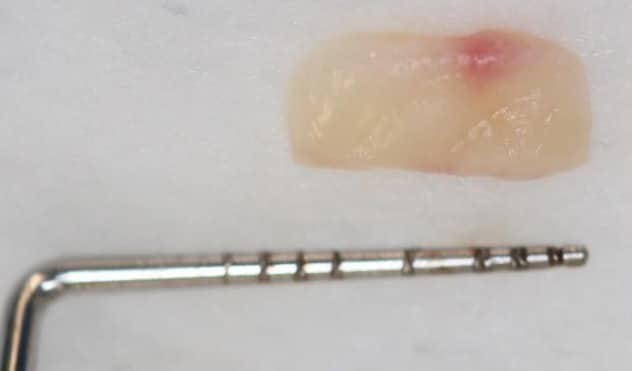

Figure 2. Surgical management of lower anterior recession using a coronally advanced flap and subepithelial connective tissue graft.

Free gingival grafts

This surgical technique first described by Bjorn 1963, and later modified by Sullivan and Atkins in 1968, is commonly used for mandibular recessions where aesthetic concerns are of less importance. The colour match to the surrounding gingival tissue is unpredictable, however this method is a predictable surgical technique to primarily increase keratinised tissue width. Some root coverage may be achieved. Over time a ‘creeping attachment mechanism’ can occur. This attachment results in the post-operative migration of the free gingival graft in a coronal direction, thereby increasing root coverage over time. Both surgical techniques can also be used around implants.

Figure 3. An epithelialised free gingival graft to increase keratinised tissue width.